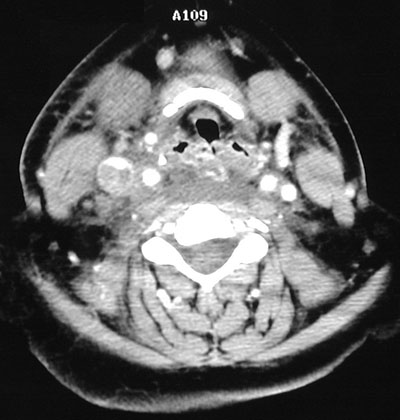

The head and neck CT scans with contrast above and below demonstrate thrombus filling and distending the internal jugular vein, with a rim of bright contrast. This thrombus extended from the superior vena cava.